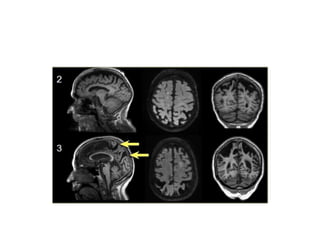

• 60 yearold man presented with incoordination of movements with tremor , with wide based staggering gait , nystagmus and scanning speech. He gives a history than his 32 year old son has similar complaints. On examination power is normal, Tone is spastic,knee and ankle reflex was absent plantar was extensor. Dymmetria, dysdiadakinesis , pendular knee jerk was present. MRI showed diffuse cerebellar atrophy

Spinocerebellar Ataxia • Autosomaldominant • SCA 1-36 types , SCA1,2,3,7,17 due to CAG triplet repeat expansion codes for glutamine Protiens termed as ATAXINS- more than -40 glutamines potentially toxic for the neurons – leads to neuronal loss and gliosis SCA 8- CTG repeat,SCA 10 forms pentanucleotide repeats • Anticipation ( earlier age on onset and aggressive course in successive generation )

present. MRI showed diffuse cerebellar

atrophy